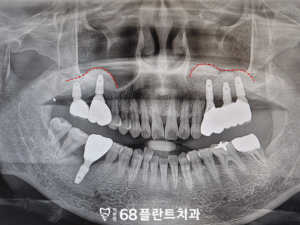

따라서 철산동치과에서는

4개 치아 발치 후 임플란트를 식립하며

위쪽 임플란트는 상악동거상술을

같이 진행하기로 하였습니다.

이렇게 상악동거상술 후

뼈가 자리를 잡고

안정화되는 기간을 충분히 거치면,

그 위에 임플란트를 안정적으로

심을 수 있는 기반이 마련됩니다.

보통 3~6개월 정도의

치유 기간이 필요하며,

이후 정밀 검사를 통해

뼈가 잘 형성되었는지 확인한 후

임플란트 식립이 진행됩니다.